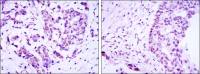

IHC-P analysis of human brain tissue using GTX55364 MDC1 (phospho Ser513) antibody.

Left : Primary antibody

Right : Primary antibody pre-incubated with the antigen specific peptide